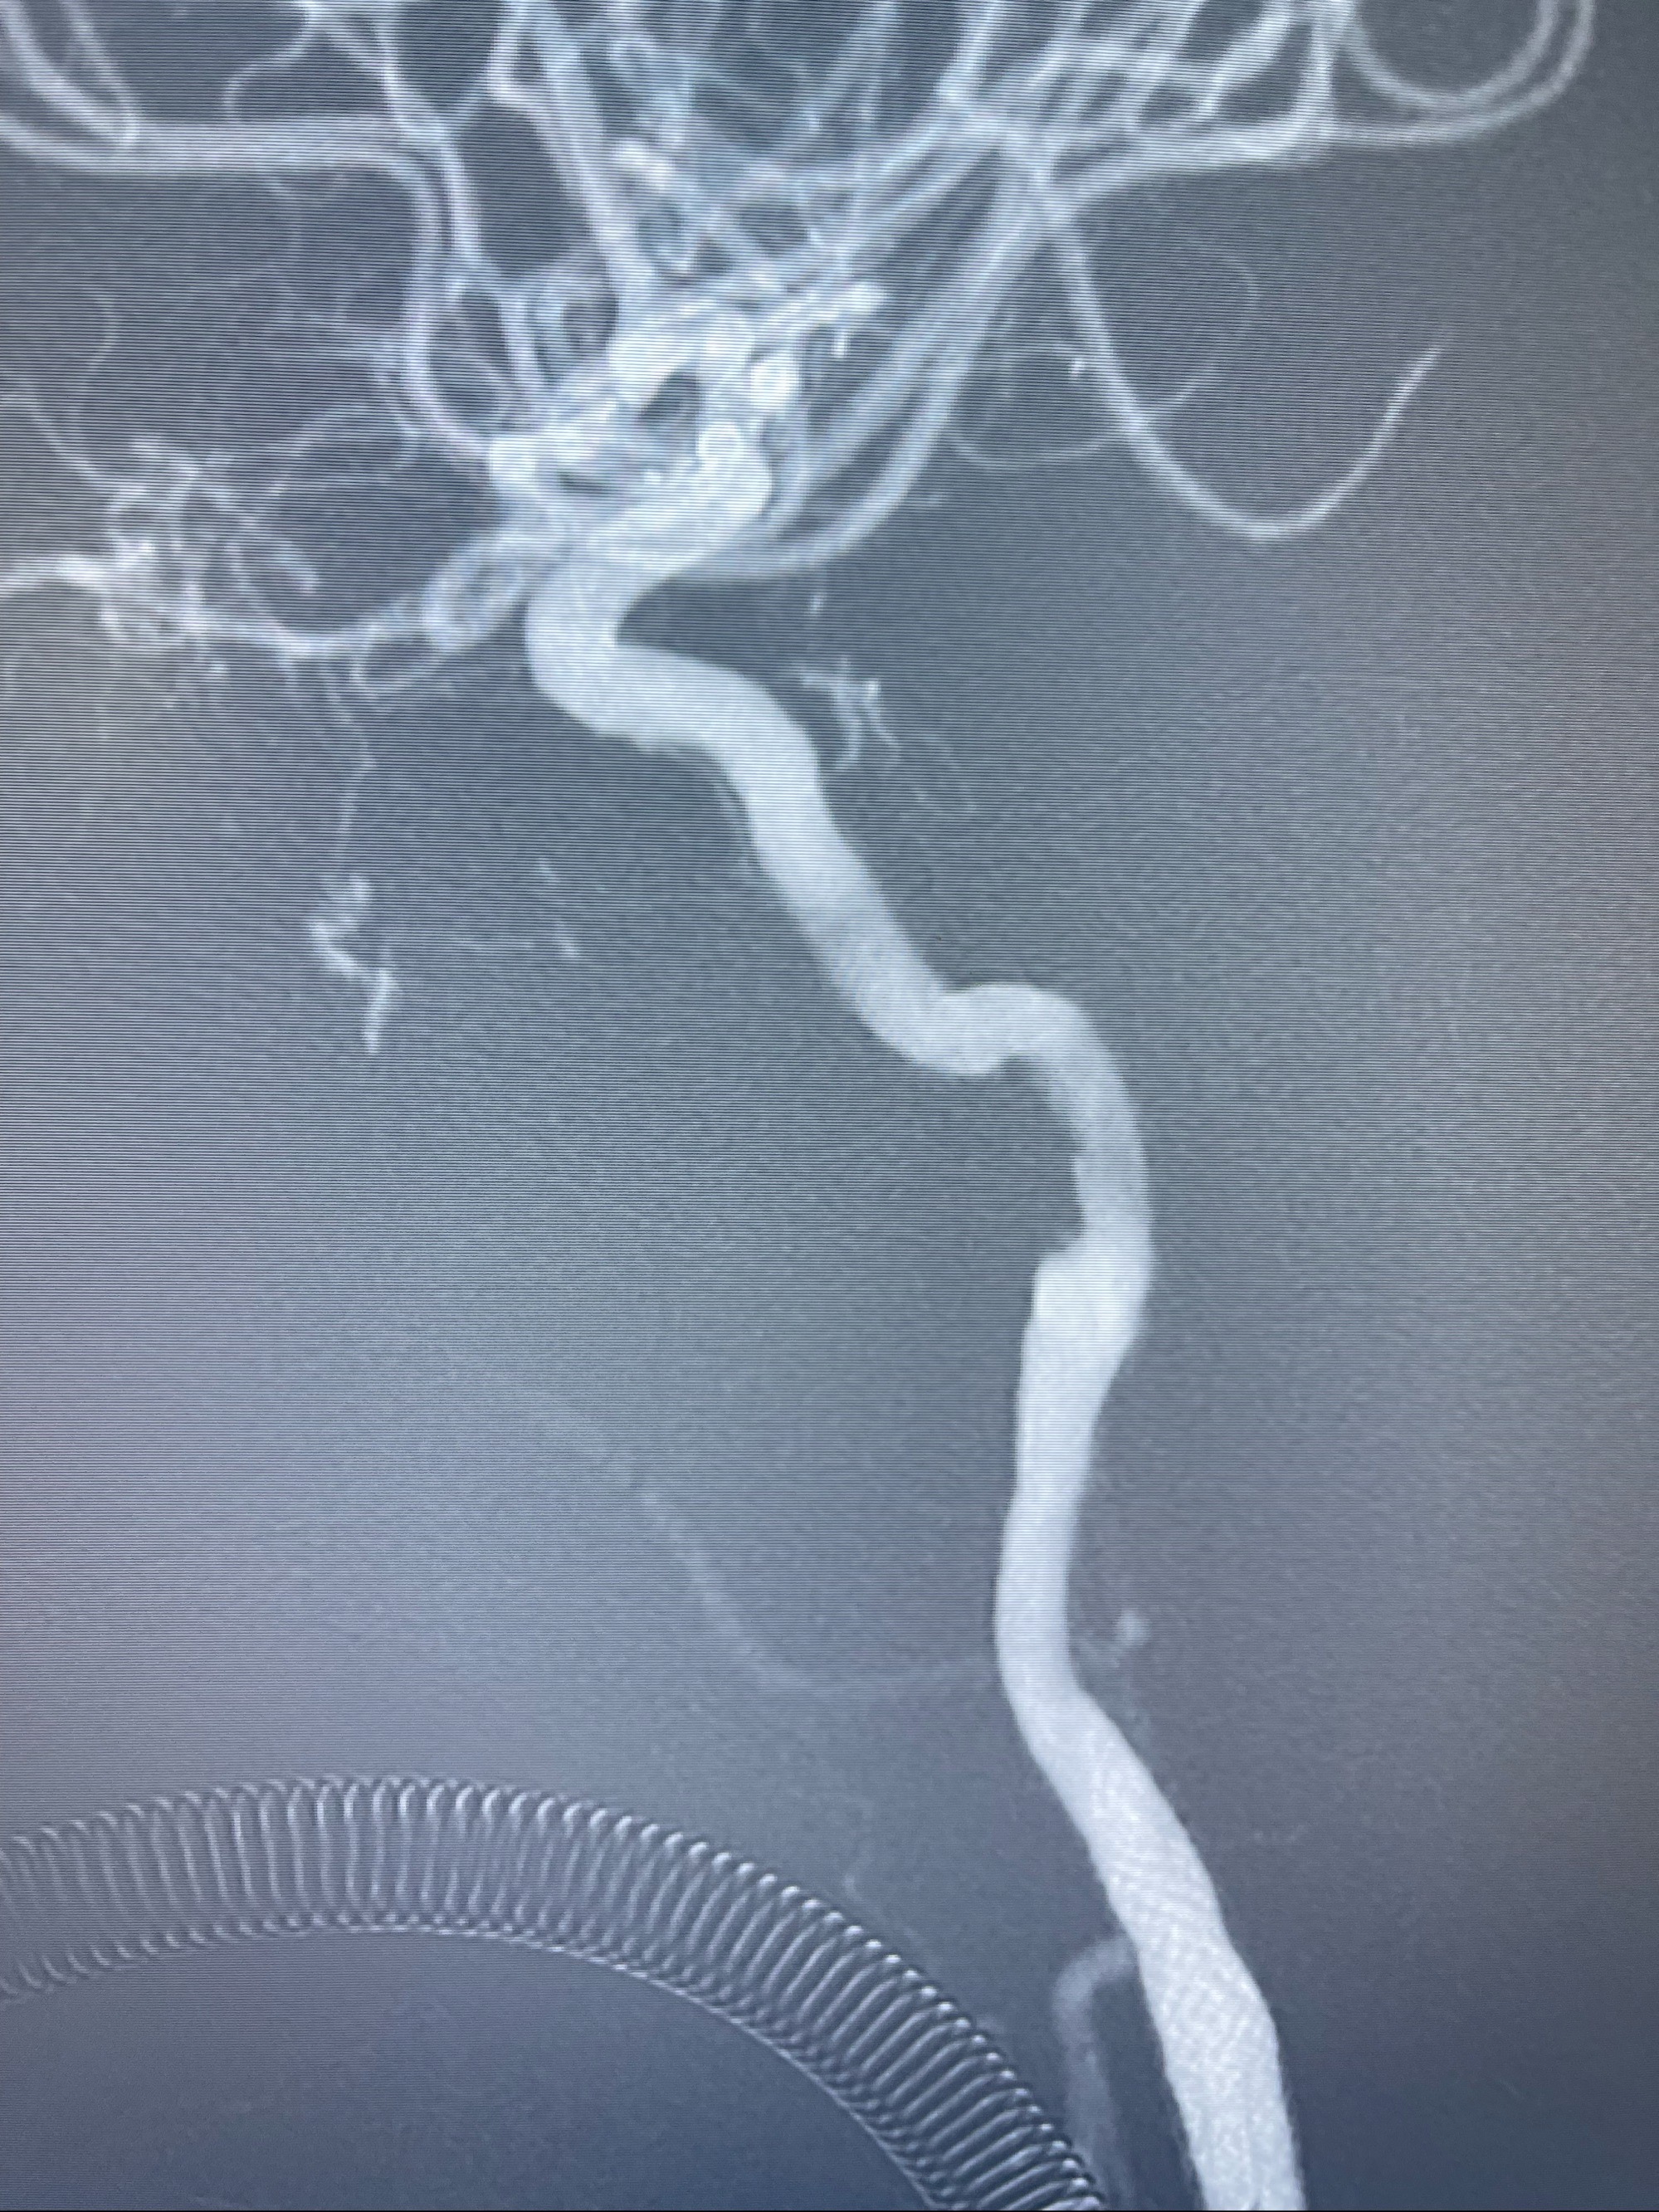

路径图下,5.5-50mmLeo支架导管在微导丝引导下超选择性插入远段Leo支架内

两枚支架部分重叠

多次确认支架位置及打开贴壁情况

支架完全打开,近心端位于原颈动脉支架远心端内

麻醉苏醒佳,遵嘱活动!

术后给予替罗非班300ug/h维持,序贯阿司匹林100mg➕泰嘉75mg口服